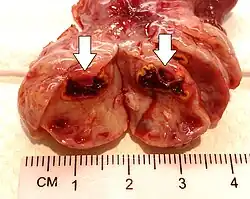

Corpus luteum cyst

A corpus luteum cyst or luteal cyst is a type of ovarian cyst which may rupture about the time of menstruation, and take up to three months to disappear entirely. A corpus luteum cyst does not often occur in women over the age of 50, because eggs are no longer being released after menopause. Corpus luteum cysts may contain blood and other fluids. The physical shape of a corpus luteum cyst may appear as an enlargement of the ovary itself, rather than a distinct mass-like growth on the surface of the ovary.